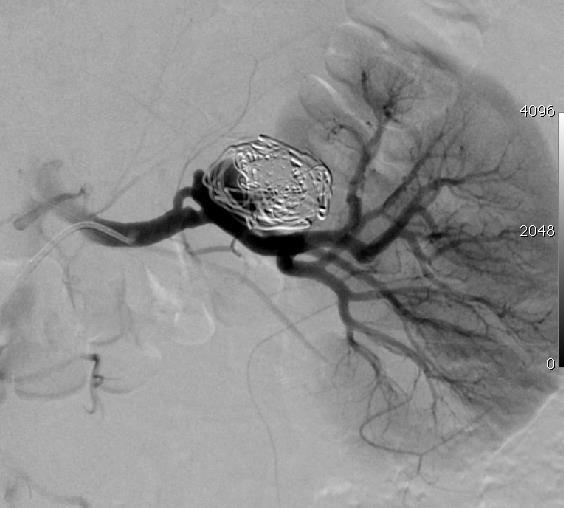

肾动脉瘤重塑技术

|

|

|

|

|

肾动脉瘤 |

微导管头进入动脉瘤腔后用球囊(4mm x 20mm)充盈后封住瘤颈的口;释放微弹簧圈到动脉瘤囊内 |

微弹簧圈对瘤囊致密填塞

coil N=41 |

栓塞后造影显示瘤腔消失 |